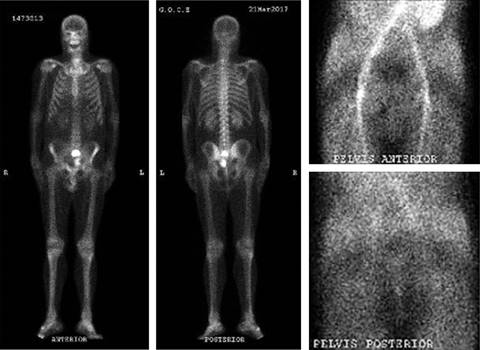

Varón de 62 años, fumador de 20 paquetes-año, con antecedentes personales de artritis reumatoide en tratamiento con certolizumab que es valorado en atención primaria por presentar episodios esporádicos de hematuria macroscópica relacionados con el ejercicio, de cuatro meses de evolución. A la exploración física presenta molestias a la palpación en fosa ilíaca derecha sin masas asociadas. Tras realización de análisis de sangre incluyendo antígeno prostático específico (PSA) y ecografía de aparato urinario y vejiga, que informa de «próstata heterogénea y mal definida, con calcificaciones y aumentada de volumen en unos 60 cm3», es remitido a urología. Se realiza una cistoscopía en la que se aprecia «litiasis de 1.5-2 cm y una neoformación papilar de aspecto superficial < 1 cm en proximidad del meato ureteral derecho», por lo que se decide llevar a cabo una cistolitotricia endoscópica y resección transuretral vesical (RTU). La liberación de la «litiasis vesical» se describe como «aspecto de tumor calcificado» y se aprecia un «tumor vesical extenso sólido de pared anterior y fondo calcificado en superficie». Ante estos hallazgos, se solicita una radiografía (Rx) de abdomen (Figura 1) y se envían muestras a anatomía patológica (AP). Posteriormente se realiza tomografía axial computarizada (TAC) abdominopélvica con contraste (Figura 2)-, que informa de «masa infiltrante exofítica que afecta a la vertiente anteroinferior de la vejiga con signos sugestivos de probable infiltración de la rama iliopubiana derecha y del músculo obturador homolateral, contactando asimismo con la vertiente anterior de la próstata, sin plano de separación grasa. Neoplasia vesical infiltrante (T4) con adenopatía sospechosa en cadena ilíaca externa derecha, sin lesiones de tracto urinario superior ni a distancia».

En ese momento el paciente es derivado al servicio de cirugía ortopédica y traumatología (COT) y tras valoración por el comité de tumores musculoesqueléticos (CTME) se realiza un estudio de extensión mediante TAC de tórax y gammagrafía ósea 99mTc-HMDP de cuerpo entero, la cual es negativa para enfermedad metastásica a distancia (Figura 6). Se decide intervención quirúrgica con el diagnóstico de condrosarcoma en zona 3 de Enneking6 (Figura 7). Se realiza exéresis ampliada de la tumoración con cistectomía radical (Figuras 8 y 9) y reconstrucción del suelo pélvico con malla sin reconstrucción ósea junto a cirujanos urológicos y del aparato digestivo.

Figura 6: Gammagrafía ósea 99mTc-HMDP de cuerpo entero. SPECT óseo y fase vascular. SPECT = Tomografía computarizada por emisión de fotón único.